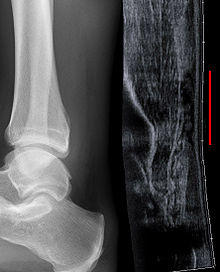

Achilles tendon rupture seen on ultrasound. Note discontinuity over several centimeters (red line). No fracture or avulsion (radiograph).

Musculoskeletal ultrasonography can be used to determine the tendon thickness, character, and presence of a tear. It works by sending extremely high frequencies of sound through the body. Some of these sounds are reflected back off the spaces between interstitial fluid and soft tissue or bone. These reflected images can be analyzed and computed into an image. These images are captured in real time and can be very helpful in detecting movement of the tendon and visualising possible injuries or tears. This device makes it very easy to spot structural damages to soft tissues, and consistent method of detecting this type of injury. This imaging modality is inexpensive, involves no ionizing radiation and, in the hands of skilled ultrasonographers, may be very reliable.

Radiography can also be used to indirectly identify Achilles tears. Radiography uses X-rays to analyse the point of injury. This is not very effective at identifying injuries to soft tissue. X-rays are created when high energy electrons hit a metal source. X-ray images are acquired by utilising the different attenuation characteristics of dense (e.g. calcium in bone) and less dense (e.g. muscle) tissues when these rays pass through tissue and are captured on film. X-rays are generally exposed to optimise visualisation of dense objects such as bone while soft tissue remains relatively undifferentiated in the background. Radiography has little role in assessment of Achilles' tendon injury and is more useful for ruling out other injuries such as calcaneal fractures.[12]